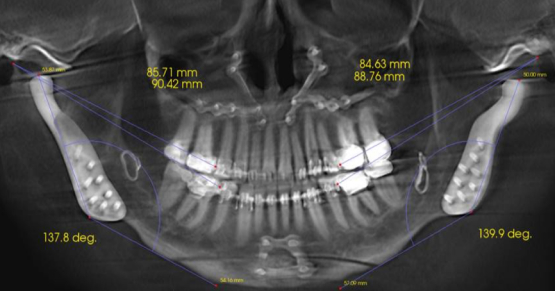

The vertical margin in full veneer crown preparation can offer an esthetic, minimally invasive, and biocompatible solution for periodontally or structurally compromised teeth. For example, this patient, who was restored as a fixed-removable combination case:

Provision of splinted crowns: Used to stabilize mobile teeth, multiple units of cross-arch braced crowns can be challenging to prepare with parallel insertion paths. The vertical margin makes this a more straightforward proposition since the technician has some degree of flexibility in margin positioning and can compensate for minor alignment errors.